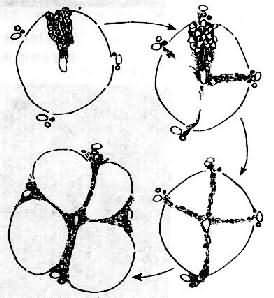

上述各种因素首先引起肝细胞脂肪变、坏死及炎症等,以后在坏死区发生胶原纤维增生。后者主要来自增生的纤维母细胞、局部的贮脂细胞及因肝细胞坏死,局部的网状纤维支架塌陷,网状纤维融合形成胶原纤维(无细胞硬化)。初期增生的纤维组织虽形成小的条索但尚未互相连接形成间隔而改建肝小叶结构时,称为肝纤维化。为可复性病变,如果病因消除,纤维化尚可被逐渐吸收。如果继续进展,小叶中央区和汇管区等处的纤维间隔互相连接,终于使肝小叶结构和血液循环被改建而形成肝硬变(图10-43)。

图10-43门脉性肝硬变假小叶形成过程示意图